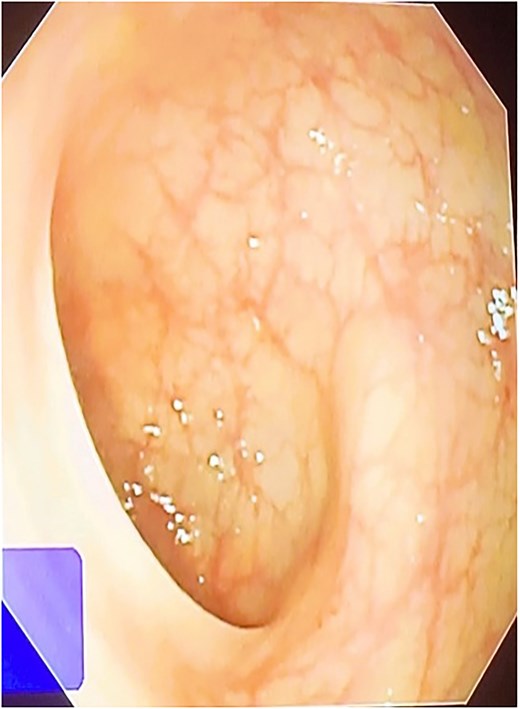

A 42-year-old male patient presented with discharge from anal regions accompanied with pain. Upon rectal examination, an internal opening was observed at 6 o’clock, ~2.5 cm above the anal verge. The external opening was located on the right thigh, 18 cm away, with an indurated tract beneath the skin. Proctoscopy revealed pus discharge from the internal opening. All relevant pre-operative investigations were done (Fig. 1).

Fistulectomy was performed in the lithotomy position. The external perianal cutaneous opening in the right buttock was used as the entry point. The tract bifurcated into two branches, forming a Y shape. One branch ended below the right levator ani muscle, while the other branch pierced the external sphincter muscle at the 6 o’clock position. (Figs 2b and 4) Both tracts were removed. The TROPIS procedure was carried out at the internal opening at 6 o’clock. There was a lateral extension of this tract, reaching up to the upper third of the thigh. The distal end of this extension was opened and the tract was thoroughly treated with the radial fiber of the diode laser (Table 1). Due to the length of the fistulous tract, FiLaC was performed (Fig. 3). A draining seton was placed from the thigh to the ischio-rectal fossa. The cavity was packed with roller gauze. The patient was discharged with instructions for regular follow up (Fig. 5).